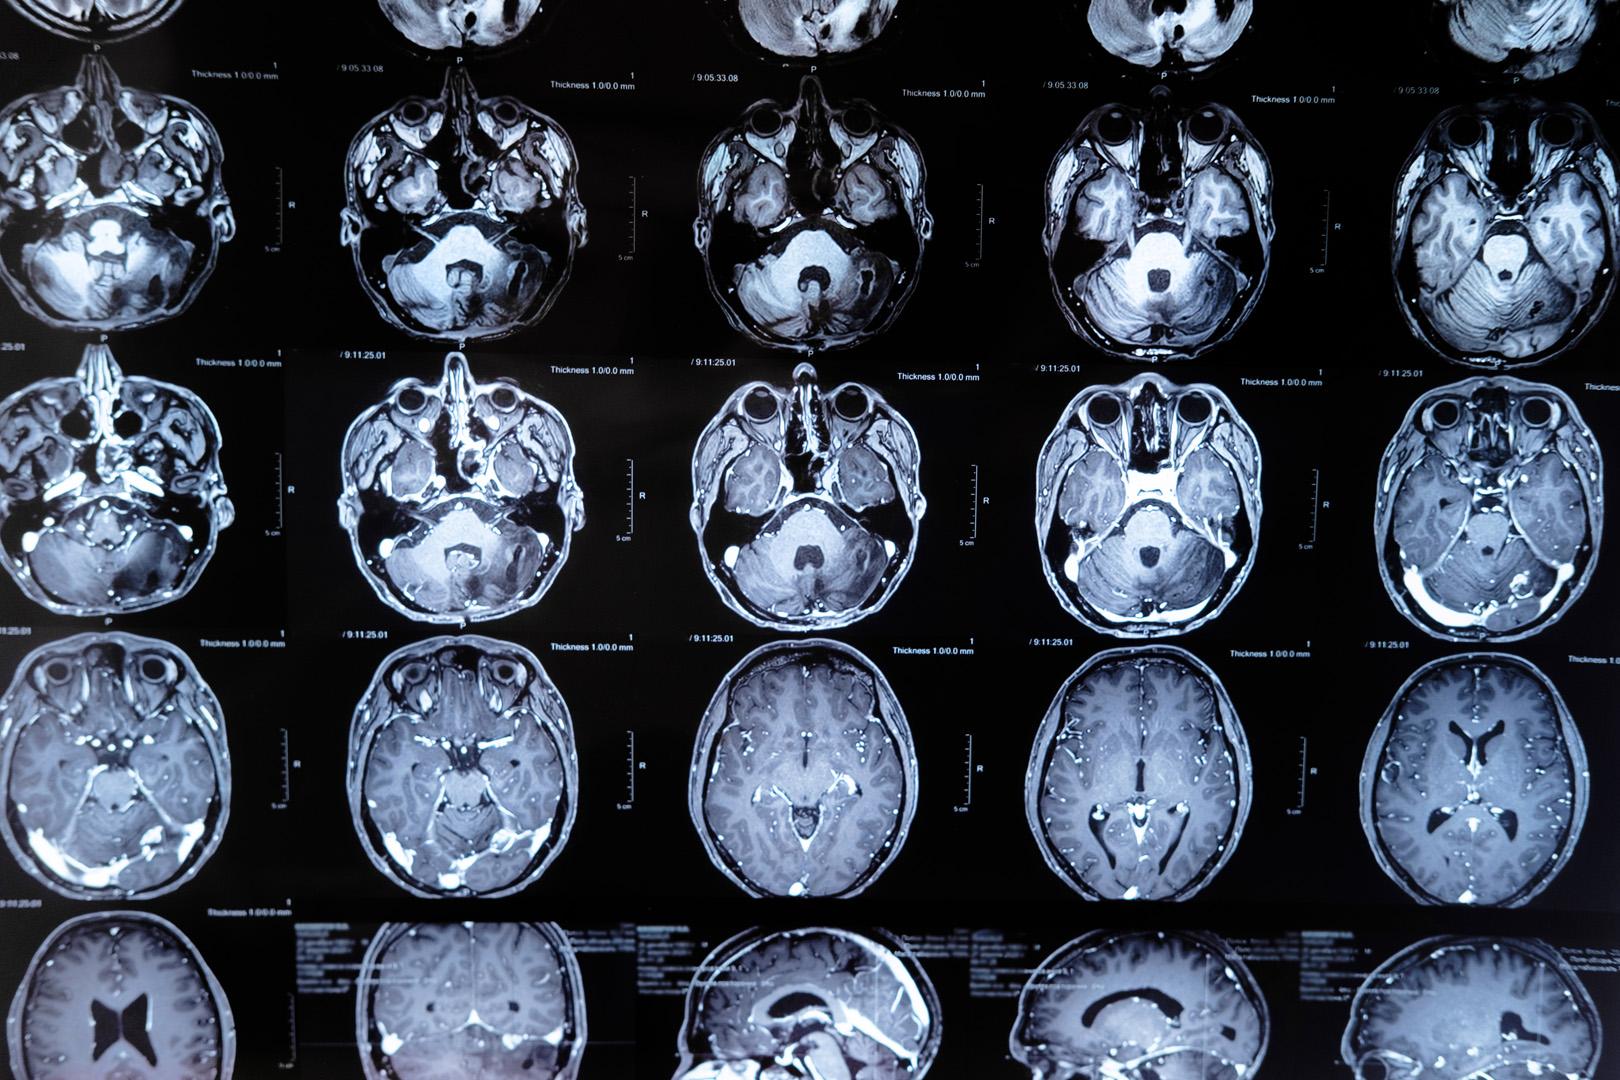

Bilim dünyasında heyecan yaratan yeni bir gelişme, Allen Enstitüsü ve HHMI'nin Janelia Araştırma Kampüsü'nde görev yapan araştırmacıların ortak çalışmasıyla ortaya çıktı. Bilim insanları, beyin hücrelerinin yalnızca dışa gönderdiği sinyalleri değil, aynı zamanda aldığı kimyasal mesajları da gerçek zamanlı olarak izleyebilen son derece hassas bir protein sensörü geliştirdi. Glutamat adlı nörotransmitterin beyindeki hareketlerini izleyebilen bu yeni teknoloji, nöronlar arası iletişimin en ince detaylarını gün yüzüne çıkarıyor. Söz konusu buluş, beynin bilgiyi nasıl işlediğine dair uzun süredir yanıt bekleyen sorulara ışık tutarken, nörolojik hastalıkların anlaşılması ve tedavisi için de umut vadediyor.

Sinirbilimin temel taşlarından biri olan glutamat, beyinde nöronlar arasında iletişimi sağlayan başlıca kimyasal haberci olarak biliniyor. Ancak glutamatın sinyalleri, son derece hızlı ve zayıf olduğundan, şimdiye dek doğrudan gözlemlenmesi neredeyse imkânsızdı. Allen Enstitüsü ve Janelia Araştırma Kampüsü'ndeki ekip, iGluSnFR4 adı verilen yeni bir protein sensörüyle bu engeli aşmayı başardı. Bu sensör, glutamatın nöronlar arasındaki hareketini anlık olarak tespit edebiliyor ve böylece beyin hücrelerinin nasıl bilgi aldığı, işlediği ve yanıt verdiği ilk kez doğrudan gözlemlenebiliyor. Araştırmacılar, bu gelişmenin beynin işleyişini anlamada kritik bir dönüm noktası olacağını vurguluyor.

Glutamat, beyindeki en yaygın nörotransmitter olarak hafıza, öğrenme ve duyguların düzenlenmesinde merkezi bir rol üstleniyor. Ancak glutamat sinyalleşmesindeki anormallikler, Alzheimer hastalığı, şizofreni, otizm ve epilepsi gibi ciddi nörolojik rahatsızlıklarla ilişkilendiriliyor. Yeni geliştirilen glutamat sensörü sayesinde, bu hastalıklarda nöronlar arası iletişimin nasıl bozulduğunu daha hassas biçimde izlemek mümkün hale geldi. Araştırmacılar, bu teknolojinin hastalıkların mekanizmasını anlamada ve yeni tedavi yöntemlerinin geliştirilmesinde önemli bir araç olacağını belirtiyor. Özellikle ilaç araştırmalarında, deneysel tedavilerin sinaptik aktivite üzerindeki etkileri artık çok daha ayrıntılı şekilde takip edilebilecek.

Bugüne dek, beyin dokusunda nöronlara gelen kimyasal sinyalleri doğrudan gözlemlemek büyük bir zorluktu. Önceki teknolojiler, ya yavaş kalıyor ya da tek tek sinapslardaki aktiviteyi yakalamakta yetersiz kalıyordu. Bu nedenle, araştırmacılar çoğunlukla yalnızca nöronlardan çıkan sinyalleri kaydedebiliyor, gelen mesajları ise gözden kaçırıyordu. iGluSnFR4 ile artık nöronların aldığı kimyasal mesajlar anlık olarak izlenebiliyor. Bu gelişme, nöronlar arası iletişimin hangi desenlerle gerçekleştiğini ve hangi sinyal kombinasyonlarının hücreleri harekete geçirdiğini anlamada yeni bir kapı aralıyor. Böylece, beynin karmaşık bilgi işleme süreçleri daha önce hiç olmadığı kadar ayrıntılı şekilde incelenebiliyor.